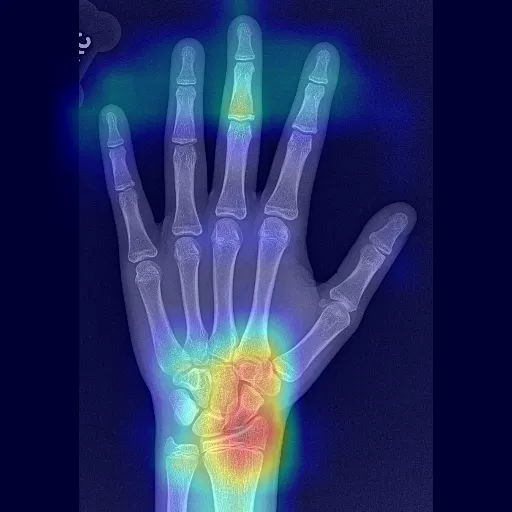

"{""label"": ""5 years"", ""confidences"": null}","The closest Greulich & Pyle bone ages are:

1) 5 years

2) 5 years, 9 months","{""path"": "".gradio/cached_examples/20/Heatmap Image/33ead32d7cadc4f26d4b/image.webp"", ""url"": ""/gradio_api/file=/tmp/gradio/e860e2b868e0d01ce87c9802cd5777b6a9bc554743c2ed8bbcb24eb9b9fa6e02/image.webp"", ""size"": null, ""orig_name"": ""image.webp"", ""mime_type"": null, ""is_stream"": false, ""meta"": {""_type"": ""gradio.FileData""}}",2024-12-16 11:45:56.361340

"{""label"": ""11 years, 9 months"", ""confidences"": null}","The closest Greulich & Pyle bone ages are:

1) 12 years

2) 11 years","{""path"": "".gradio/cached_examples/20/Heatmap Image/f2d4910659006b78e8b4/image.webp"", ""url"": ""/gradio_api/file=/tmp/gradio/4f51148a75979962de3db405711cd85b91f7953a5bfd4345b3f75769727a1fc2/image.webp"", ""size"": null, ""orig_name"": ""image.webp"", ""mime_type"": null, ""is_stream"": false, ""meta"": {""_type"": ""gradio.FileData""}}",2024-12-16 11:45:58.619854